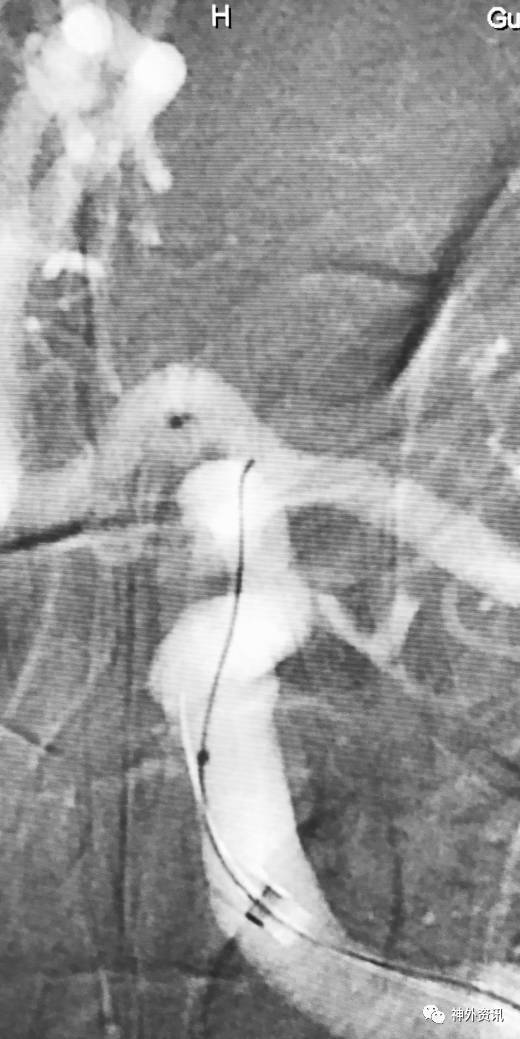

病例一

眼动脉动脉瘤,支架完全释放后,微导管成袢逆行到位

病例二

眼动脉动脉瘤,支架释放前,微导管成袢逆行到位